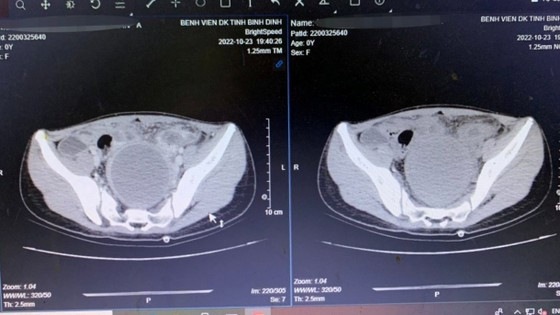

| Kết quả xét nghiệm, chụp phim cho cháu bé. |

Qua thăm khám, các bác sĩ nhận định đây là trường hợp dị dạng tử cung đôi có tắc nghẽn âm đạo. Qua siêu âm ổ bụng ghi nhận có ổ dịch không đồng nhất ở hạ vị, bệnh nhân chỉ có thận độc nhất bên phải.

Bệnh nhân sau đó được cho quét MRI ổ bụng để xác định chẩn đoán và phẫu thuật cấp cứu trì hoãn để xẻ túi cùng âm đạo thoát khối máu tụ trong lòng tử cung bế tắc.